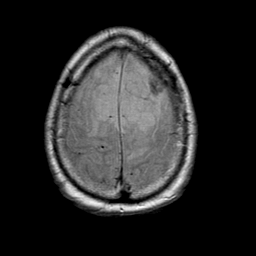

Meningioma, MR Study #1 -- Slice #18

[Home][Help][Clinical] Slice 18